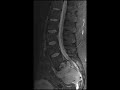

Multiple Myeloma

There is a relatively homogeneous mildly expansile T1 hypointense, T2 isointense, STIR hyperintense mass replacing a large portion of the sacrum and moderately narrowing multiple neural foramina. The CT image shows the lytic nature of this mass with no matrix identified. The diffuse heterogeneity of the bone marrow gives us a clue as to the etiology of this mass which on pathology showed it to be a plasma cell neoplasm in a patient with a history of multiple myeloma. The differential diagnosis in this case would include giant cell tumor, metastasis, lymphoma, and possibly chordoma which often has intratumoral calcifications.